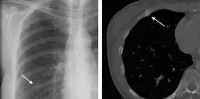

According to a study presented this week at the annual meeting of the Radiological Society of North America (RSNA), researchers at the Mayo Clinic have found that many children receive chest x-rays that may be unnecessary and have no clinical benefit.

"Chest x-rays can be a valuable exam when ordered for the correct indications," said Ann Packard, MD, radiologist at the Mayo Clinic in Rochester, Minnesota. "However, there are several indications where paediatric chest x-rays offer no benefit and likely should not be performed to decrease radiation dose and cost."

The analysis showed that the x-ray exams did not alter clinical treatment in approximately 88 percent of the patients. Thirty-nine of the 330 non-excluded x-rays for chest pain were positive for pneumonia, bronchial inflammation, trauma, or other conditions.

"Approximately 12 percent of the chest x-rays for chest pain were positive and included respiratory symptoms such as cough, fever or trauma," Dr. Packard said. "There were no positive findings in any chest x-ray for syncope, dizziness, spells, cyclical vomiting or POTS for the past five years, even in our tertiary care centre with referrals for rare diseases or unusual presentations."